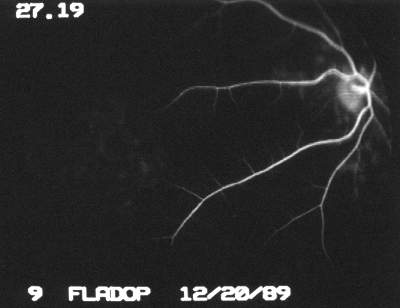

Abb. 11 Phase der retinalen arteriellen Pulsationen (FLADOP, IOD = 93 mmHg) |

. Bei Unterschreiten des systolischen Blutdrucks der Zentralarterie öffnet sich dieselbe im Bereich der Lamina cribrosa. Das Fluoreszein breitet sich nun pulsierend in den retinalen Arteriolen aus. Gelegentlich läßt sich beobachten, daß das in der Systole einströmende Fluoreszein während der Diastole wieder zurückgepreßt wird. Erst bei weiter absinkendem intraokularen Druck wird dann ein Voranschreiten der Farbstoff-Front sichtbar. Da durch den weiterhin erhöhten intraokularen Druck der Einstrom von Fluoreszein in die Choriokapillaris verhindert wird, wird das retinale Kapillarbett besonders kontrastreich dargestellt (Abb. 11) . Das retinale Kapillarbett füllt sich nicht gleichmäßig. Zunächst öffnen sich die Netzhautkapillaren der peripapillären Region. Erst bei weiterem Absinken des intraokularen Drucks werden die Kapillarnetze der perimakulären Region und der Netzhautperipherie perfundiert. Gelegentlich erkennt man, daß benachbarte Kapillarnetze der Netzhaut, die den gleichen Abstand zur Papille haben, sich nicht gleichzeitig, das heißt bei gleichem intraokularen Druck öffnen. Vor allem peripapillär lassen sich solche nebeneinander liegende Kapillarabschnitte mit unterschiedlichem Füllungsverhalten nachweisen. |